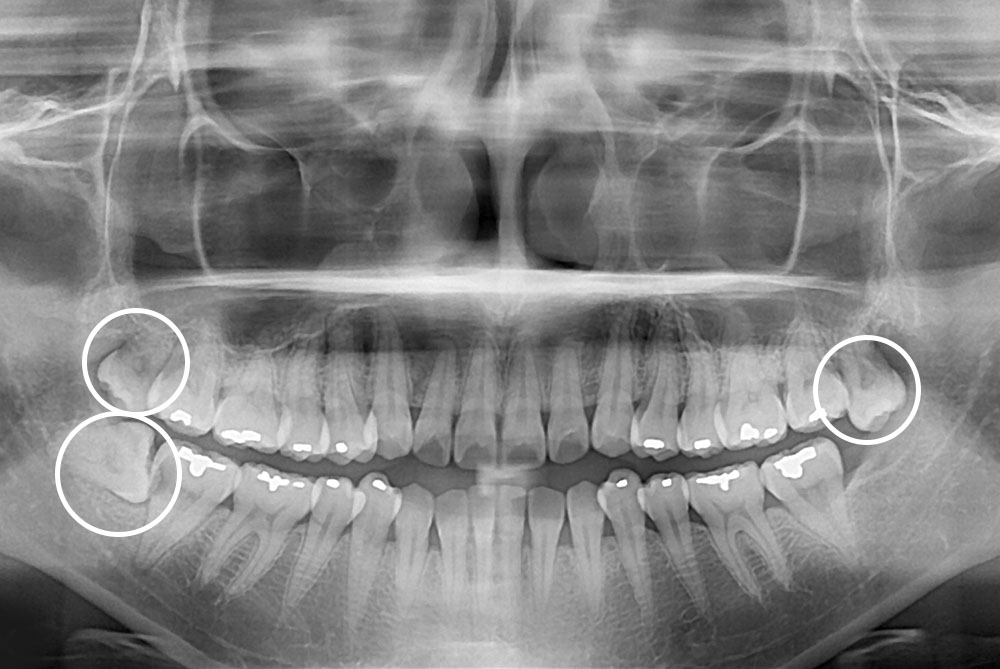

[사랑니] 매복 사랑니 발치

치료후 : 2023-07-22

세종치과는 구강악안면외과학 박사이신 원장님이 발치하는 치과입니다.